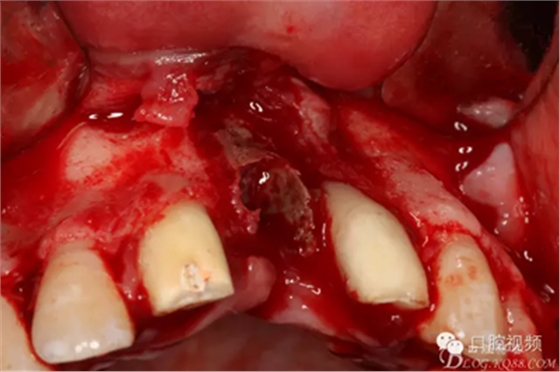

圖8.切開、翻瓣、完整暴露壞死部分牙槽骨